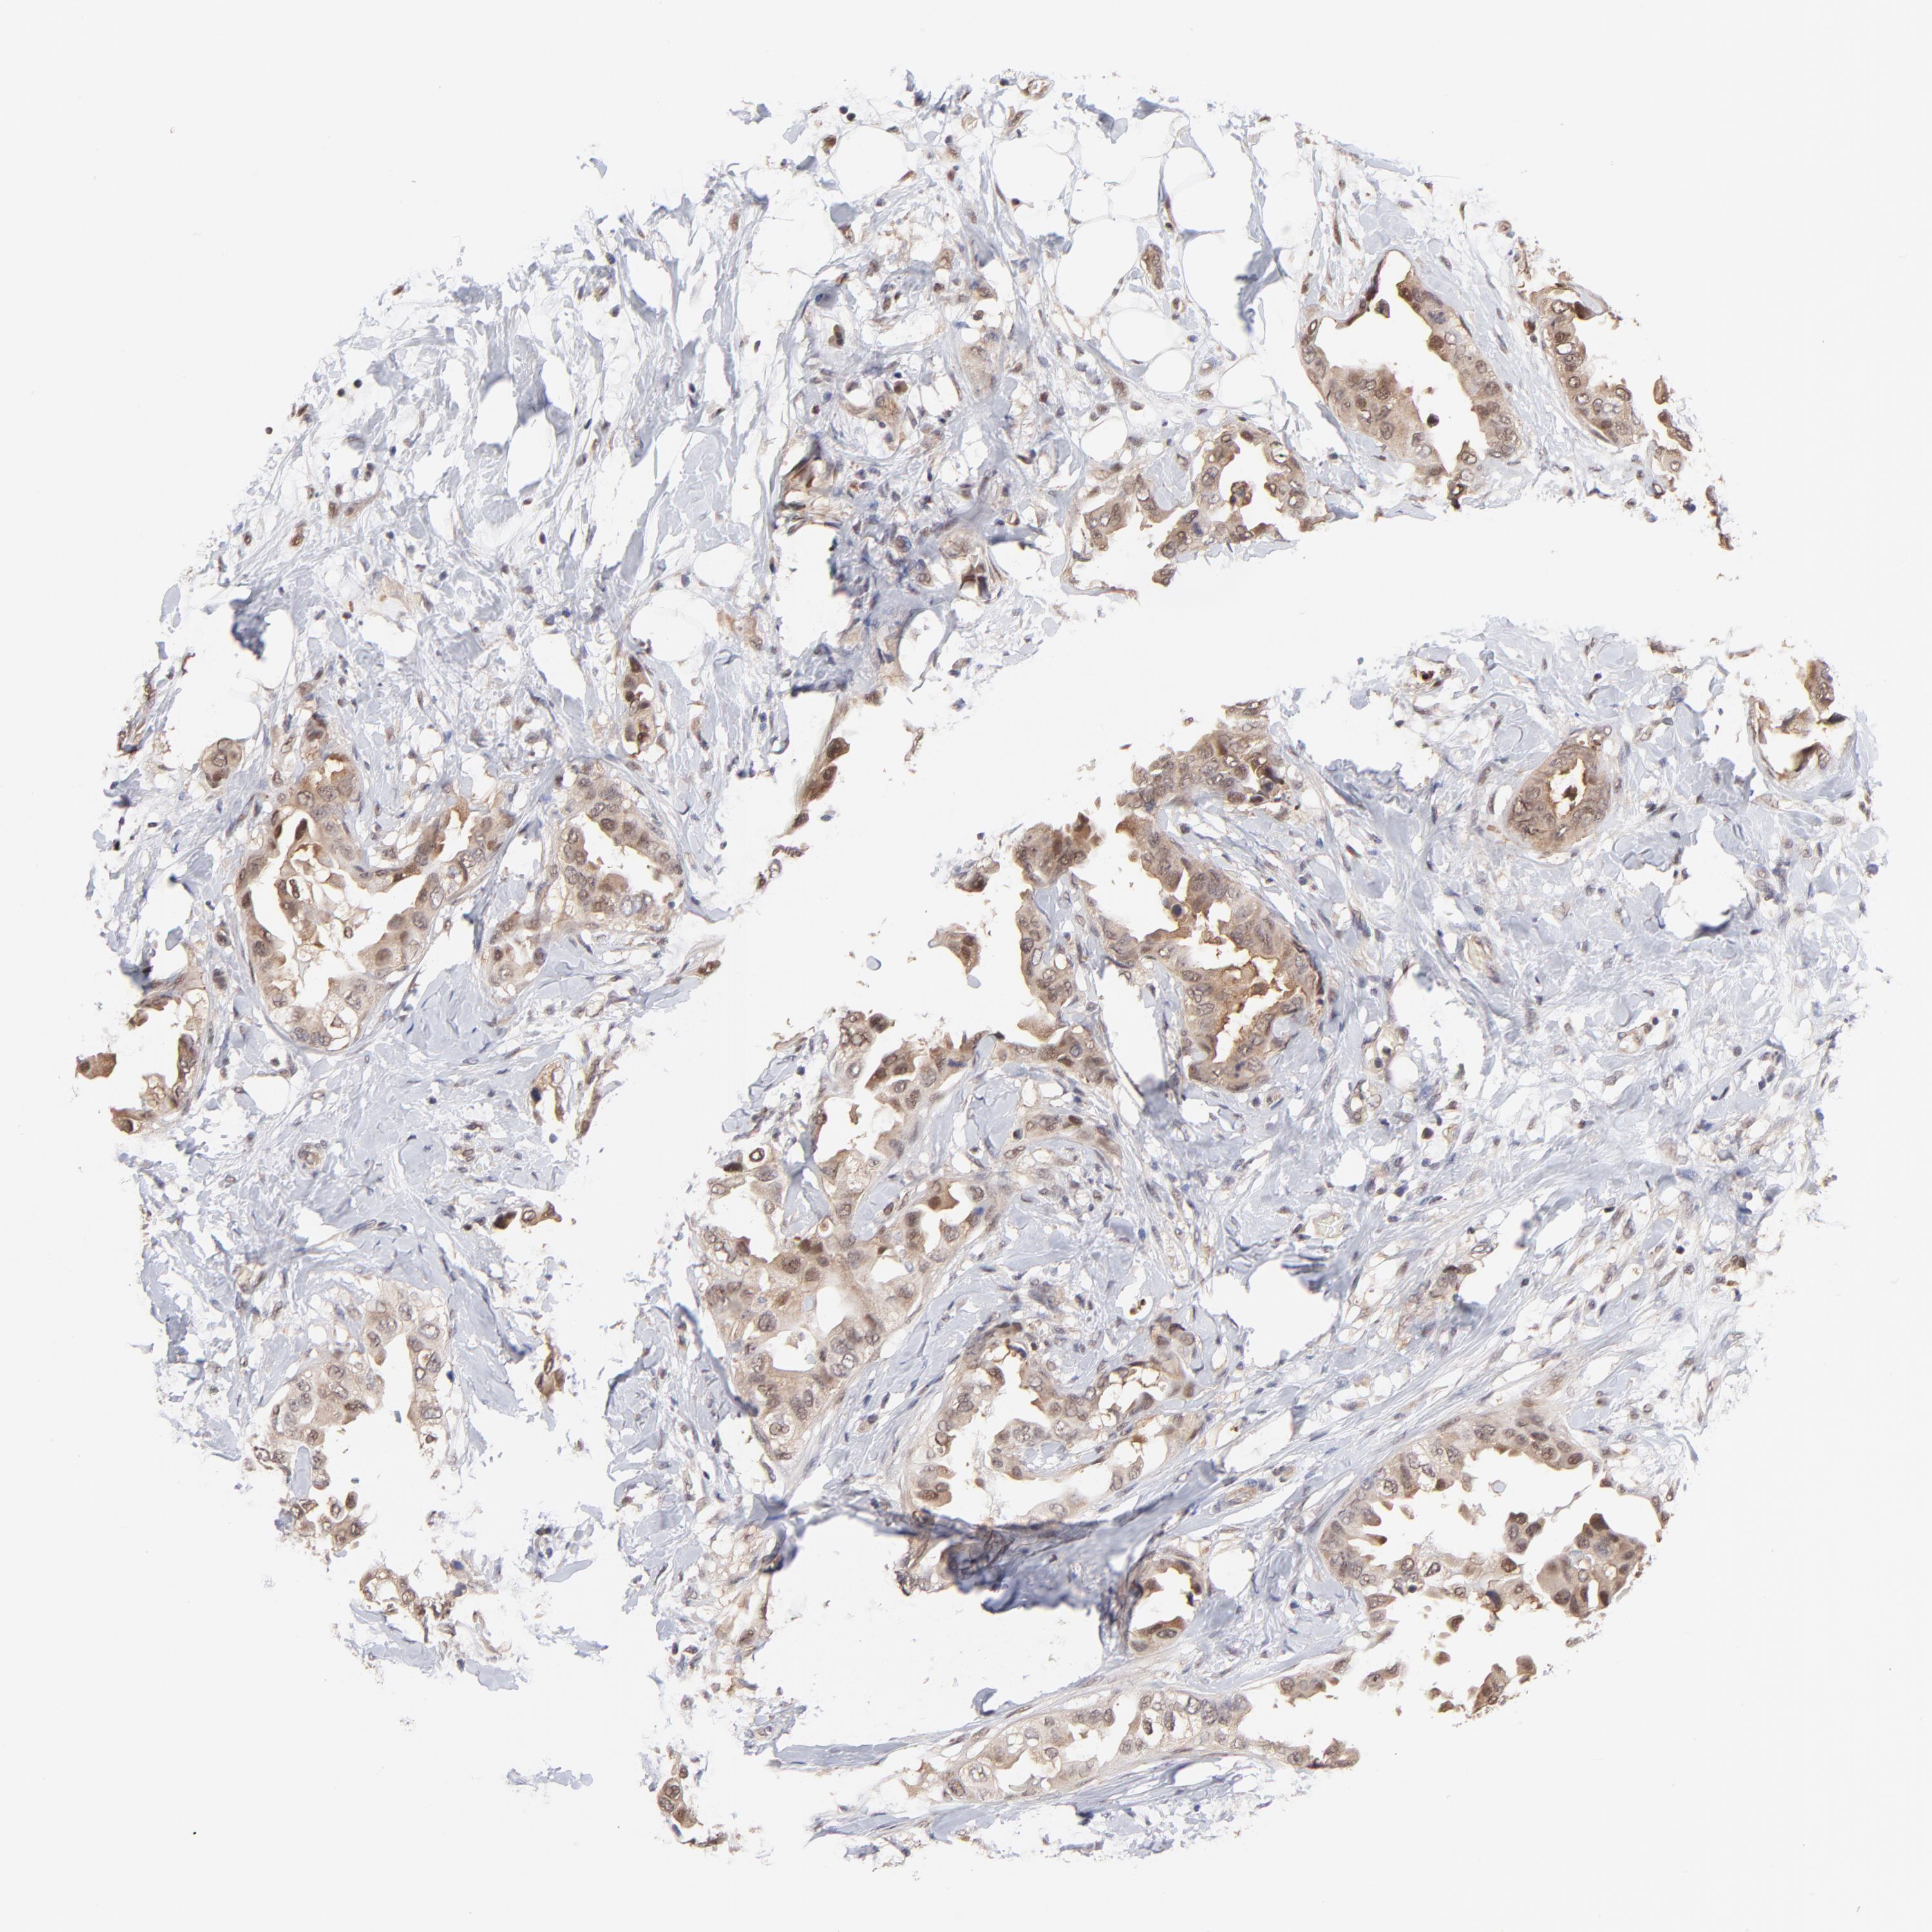

CANCER BREAST CANCER Show tissue menu

BRCA TCGA BRCA VALIDATION PROTEIN EXPRESSION